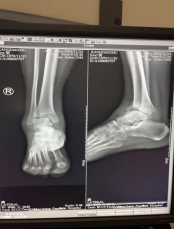

术前影像资料